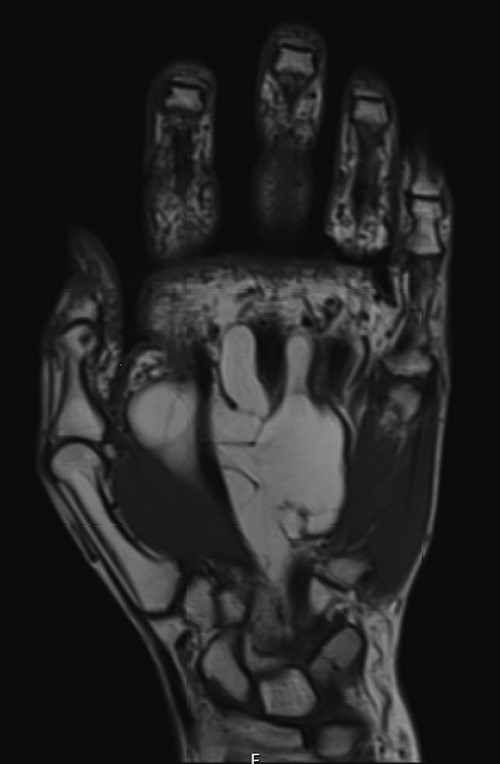

The patient underwent nerve conduction studies, which suggested a carpal tunnel lesion on the left. Magnetic resonance imaging (MRI) of the left hand confirmed the presence of a large, lobulated and well-defined fatty lesion in the palm centred between the flexor tendons and metacarpals, with dorsal and volar extensions (Fig. 1), and a proximal component within the carpal tunnel causing median nerve compression (Fig. 2). The investigations were discussed at the regional sarcoma multidisciplinary team meeting and findings were suggestive of a benign lipoma.

Coronal section demonstrating small proximal extension into carpal tunnel with resultant median nerve compression.